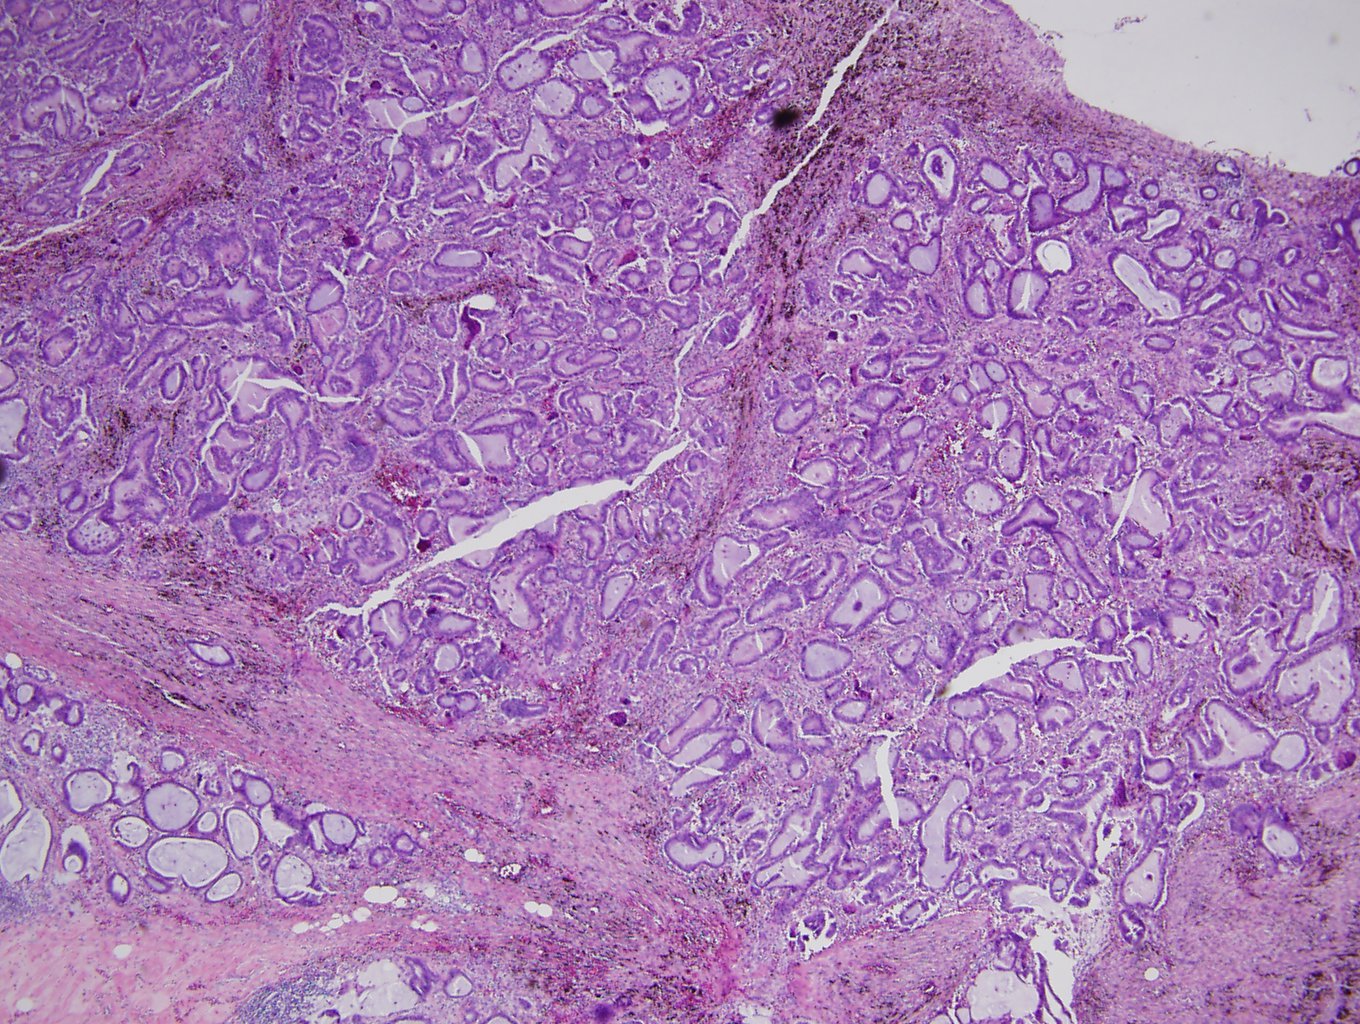

Picture144 year old female with 2.8 cm midline tongue mass

What's the underlying condition?

1. Rhabdomyoma

2. Paraganglioma

3. Metastatic renal cell

4. ...